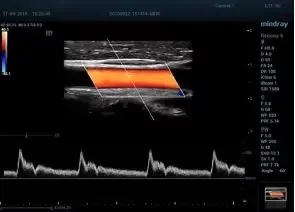

Smart Doppler интеллектуальная оптимизация доплеровских режимов

Smart Track автоматическая подстройка расположения и угла наклона рамки цветового допплера с автоматическим отслеживанием положения контрольного объема